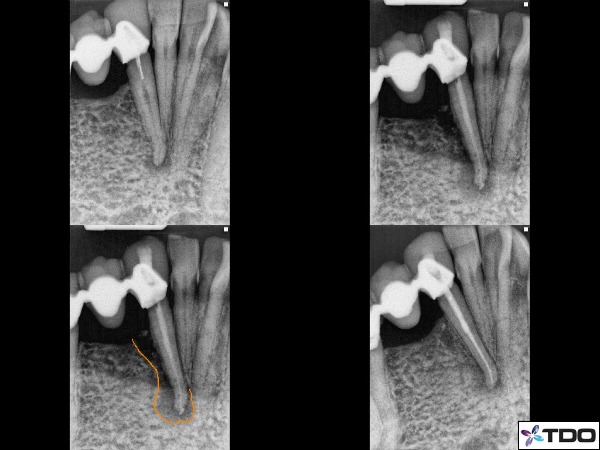

Fig.10 This was a unique case in which the patient came with an original condition shown in the upper left x-ray. She did not return to our office for treatment until 7 months later with swelling, pain, class 2 mobility, and a deep distal root probing to the apex. The x-ray of the upper right side shows the lateral bone loss with CaOH in the canal. I had put CaOH in this canal for 2 months over the course of 3 appointments. The orange line shows the amount of lateral bone loss. The final radiograph in the lower right shows reconstitution of the ligament space in just two months. The probing had reduced to 5mm and very little mobility.

The presentation of this case was that of a buccal fistula just below the free gingival margin and deep isolated probing into the furcation. Tooth was treated over 2 visits with one month of calcium hydroxide. The fistula had healed and the probing reduced to 4mm at the buccal furcation. Completion appointment x-ray in the upper right. X-ray at the lower right is the 5 month recall showing excellent furcal bone fill.